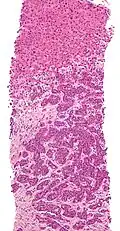

Micrograph of thyroid cancer (papillary thyroid carcinoma) in a lymph node of the neck. H&E stain

Micrograph of thyroid cancer (papillary thyroid carcinoma) in a lymph node of the neck. H&E stain -